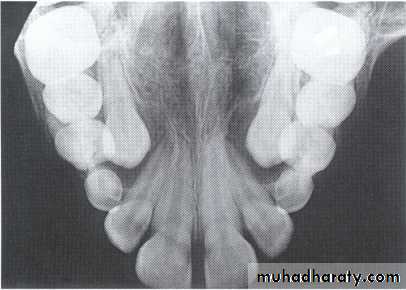

Dentigerous CystIt forms around the crown of an unerupted or supernumerary tooth at CEJ.

Some dentigerous cysts are eccentric, developing from the lateral aspect of the follicle so that they occupy an area beside the crown instead of above the crown.

It displace and resorb adjacent teeth.

It commonly displaces the associated tooth

in an apical direction.